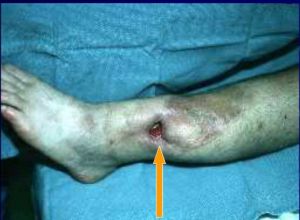

3、有竇道數量不一,流膿,不暢時可包性發作。

2、隨時觀察傷口變化,如傷口的大小、形狀、邊緣與顏色,以及肉芽組織的生長情況和膿液的多少、性質、顏色、根據情況辨證用藥。